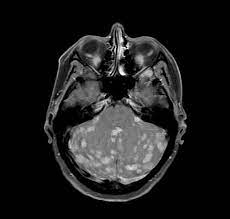

Signs Of Metastatic Breast Cancer In Brain / Metastatic Breast Cancer Warning Signs To Watch For - The most common types of cancer that cause metastatic brain tumors are cancers of the lung, breast, skin ( melanoma ), colon, kidney and thyroid gland.. Symptoms of brain metastases symptoms of brain metastases depend on the location, size and number of growths in the brain, or the amount of swelling. Jaundice or swelling in the belly, when cancer has spread to the liver. Though symptoms vary from patient to patient, common brain metastasis symptoms include: Pain and fractures, when cancer has spread to the bone. According to the national breast cancer foundation, the symptoms of metastatic breast cancer vary as far as type and severity depending on the site of metastasis (spreading).

Stroke or brain attack, in which blood supply to the brain is cut off; They are typically worse in the morning and lessen as the day goes on. Primary brain cancer occurs when a tumor develops in the brain while metastatic, however, refers to cancer that originated elsewhere in the body and then traveled to the brain. On the following pages you can read about: Though symptoms vary from patient to patient, common brain metastasis symptoms include:

Metastatic Breast Cancer Warning Signs To Watch For from images.ctfassets.net Nausea (feeling sick) or vomiting (being sick) can be caused by secondary breast cancer in the brain or elsewhere in the body, its treatment or emotional side effects such as anxiety. Headaches, sometimes with nausea and vomiting. Weakness of one side of the body, numbness, or tingling in the extremities: Stereotactic radiosurgery for brain metastasis. Some common signs of metastatic cancer include: Vomiting due to brain metastases tends to become worse and more frequent over time. Hemiparesis, weakness or paralysis of one side of the body, was the third most common neurological symptom of brain metastases in one study. The most common types of cancer that cause metastatic brain tumors are cancers of the lung, breast, skin ( melanoma ), colon, kidney and thyroid gland.

Signs and symptoms caused by brain metastases can vary based on the location, size and rate of growth of the metastatic tumors.

Metastatic breast cancer happens when the cancer spreads beyond the breast and lymph nodes, usually to the bones, liver, lungs, or brain. Headaches may be caused by a tumour pressing on the brain, swelling caused by a fluid buildup around the brain (called edema), bleeding or hydrocephalus. The symptoms of metastatic breast cancer can be very different depending on the location of the cancer: 9 warning signs of brain cancer. Primary brain cancer occurs when a tumor develops in the brain while metastatic, however, refers to cancer that originated elsewhere in the body and then traveled to the brain. In most cases, you also would continue with systemic treatments such as hormonal therapy, chemotherapy, and/or targeted therapies. Symptoms of brain metastases symptoms of brain metastases depend on the location, size and number of growths in the brain, or the amount of swelling. Bone, lung, brain, and liver. Symptoms can include sudden weakness or numbness on one side of the body, headache, trouble speaking, vision changes, dizziness and/or loss of balance Stroke or brain attack, in which blood supply to the brain is cut off; Vomiting due to brain metastases tends to become worse and more frequent over time. These are caused by a tumor creating pressure inside the skull, squeezing nearby brain tissue. Constant back, bone, or joint pain

These are the symptoms to watch for according to where mbc. Symptoms of breast cancer that has spread to the brain can include headache, changes in speech or vision, memory problems, and others. Other signs and symptoms of brain metastases include: Pain and fractures, when cancer has spread to the bone. Symptoms can include sudden weakness or numbness on one side of the body, headache, trouble speaking, vision changes, dizziness and/or loss of balance

Metastatic And Triple Negative Breast Cancer Challenges And Treatment Options Springerlink from media.springernature.com Signs and symptoms caused by brain metastases can vary based on the location, size and rate of growth of the metastatic tumors. it is common for people with metastatic breast cancer to develop metastases at multiple sites. An estimated 150,000 to 200,000 people are diagnosed with a brain metastasis each year, compared to about 17,000 diagnoses for primary. Not everyone with a brain metastasis will have symptoms but most do. Brain metastases are also much more common. Some common signs of metastatic cancer include: Bone, back, neck, or joint pain. It's important for your doctor to try to find out the cause so that it can be managed effectively.

In other cases, the body is able to. Persistent, progressively worsening headaches or pressure to the head There are two types of brain cancer known as primary and metastatic. The symptoms caused by a brain metastasis depend on the tumor's location. The women with brain metastasis, who had not yet developed symptoms at the time the metastases to the brain were discovered survived, on average, 10.4 months. Primary brain cancer occurs when a tumor develops in the brain while metastatic, however, refers to cancer that originated elsewhere in the body and then traveled to the brain. Metastases can push on or cause swelling in specific areas causing specific symptoms. Local therapies for brain metastasis include surgery and different types of radiation therapy. According to the national breast cancer foundation, the symptoms of metastatic breast cancer vary as far as type and severity depending on the site of metastasis (spreading). Symptoms can include sudden weakness or numbness on one side of the body, headache, trouble speaking, vision changes, dizziness and/or loss of balance These are the symptoms to watch for according to where mbc. Learn the signs and symptoms of metastasis, how you can make. The most common symptom of brain metastases is a headache.

The most common breast cancer metastasis sites are the bones, the lungs, the brain, and the liver. Headaches may be caused by a tumour pressing on the brain, swelling caused by a fluid buildup around the brain (called edema), bleeding or hydrocephalus. Brain surgeon and researcher rahul jandial of city of hope cancer center near los angeles explains common symptoms that could suggest brain metastasis in cancer survivors. Learn the signs and symptoms of metastasis, how you can make. They are distinct from primary brain tumors, which start in the brain.

Symptoms of brain metastases symptoms of brain metastases depend on the location, size and number of growths in the brain, or the amount of swelling. Other signs and symptoms of brain metastases include: Nausea (feeling sick) or vomiting (being sick) can be caused by secondary breast cancer in the brain or elsewhere in the body, its treatment or emotional side effects such as anxiety. Brain metastases are growths that spread to the brain from a cancer in another part of the body. Or, the cause of a symptom may be a different medical condition that is not cancer. However, for about 17% of women in this group, the brain is the only site of metastasis. The symptoms of metastatic breast cancer can be very different depending on the location of the cancer: They are distinct from primary brain tumors, which start in the brain. Signs and symptoms of brain metastases include: Headache, sometimes with vomiting or nausea mental changes, such as increasing memory problems An estimated 150,000 to 200,000 people are diagnosed with a brain metastasis each year, compared to about 17,000 diagnoses for primary. Persistent, progressively worsening headaches or pressure to the head Primary brain cancer occurs when a tumor develops in the brain while metastatic, however, refers to cancer that originated elsewhere in the body and then traveled to the brain.